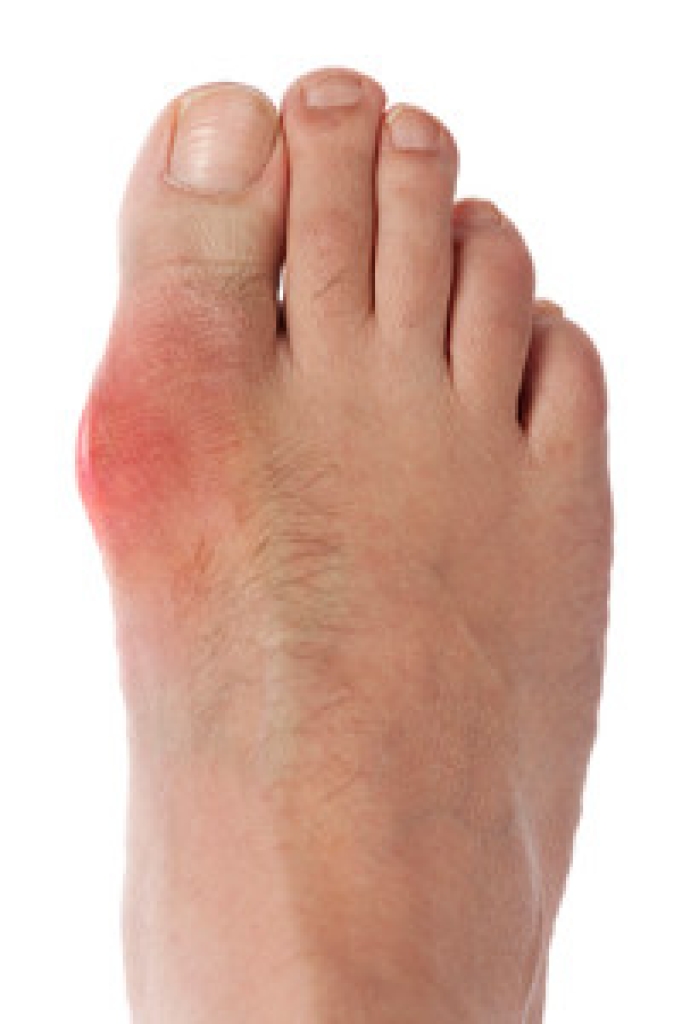

Hammertoe is a foot deformity that affects the joints of the second, third, fourth, or fifth toes of your feet. It is a painful foot condition in which these toes curl and arch up, which can often lead to pain when wearing footwear.

Symptoms

- Pain in the affected toes

- Development of corns or calluses due to friction

- Inflammation

- Redness

- Contracture of the toes